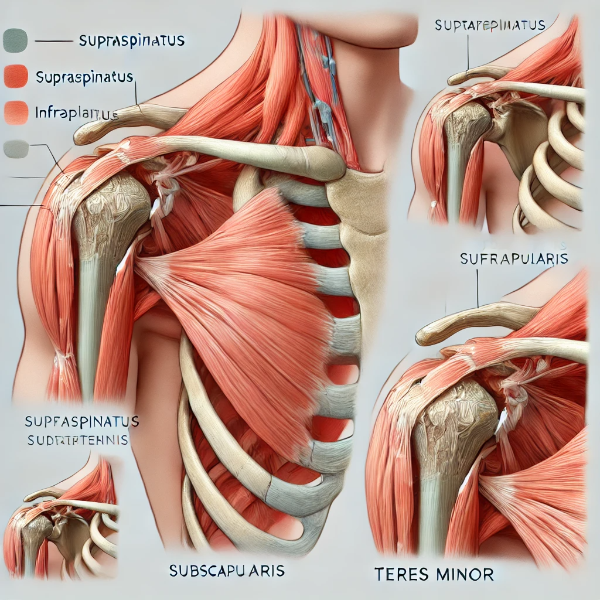

회전근개파열은 어깨의 네 개의 근육과 힘줄로 구성된 회전근개(rotator cuff)가 손상된 상태를 말합니다. 이 회전근개는 어깨 관절을 안정화하고 팔을 들어 올리거나 회전하는 데 필수적인 역할을 합니다. 특히, 어깨는 전신에서 가장 가동 범위가 넓은 관절 중 하나로, 일상적인 동작부터 스포츠 활동까지 많은 움직임을 수용해야 하기 때문에 쉽게 손상될 수 있습니다. 회전근개파열은 이러한 어깨 기능을 저해하는 주요 요인으로 작용하며, 심한 경우 일상적인 생활에도 큰 불편을 초래할 수 있습니다.